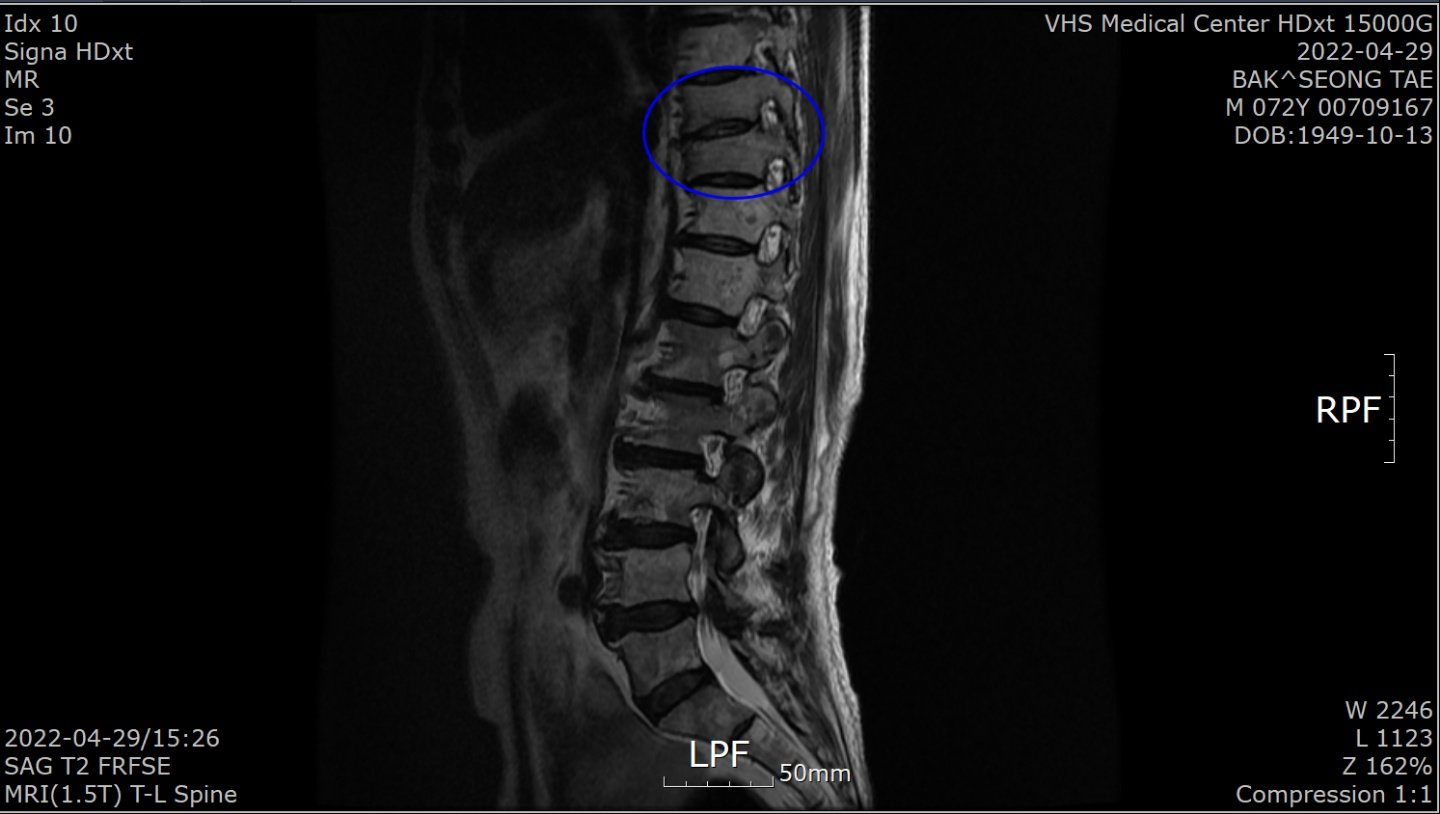

“1월 말 허리가 아파 병원에 갔더니 전립선암 말기라고 하더라고요. 전 베트남 참전용사로 국가유공자라 중앙보훈병원에서 진단 받았습니다. PSA(Prostate Specific Antigen·전립선 특이항원·전립선암의 선별검사 및 치료 판정을 위한 종양지표지자 검사)가 935 ng/mL라는 겁니다. PSA 4 ng/Ml 이하가 정상이라는데…. 너무 놀라서 그동안 아무 증상이 없었다고 했더니 전립선암은 증상이 없다 갑자기 나타난다고 하더군요. 전이가 돼 흉추 9, 10번이 시커멓게 썩었다고 하더군요. 참 나…. 방법이 죽을 방법 밖에 없다니. 하느님이 원망스러웠습니다.”

4월 29일 검사에서 PSA 수치가 0.059ng/mL로 떨어진 것이다. 그는 “MRI(자기공명촬영) 결과 새까맣던 흉추도 하얗게 정상으로 돌아왔다”고 했다. 말기암 판정 5개월여 뒤인 7월 29일 검사에선 PSA가 0.008 ng/mL로 떨어져 있었다.